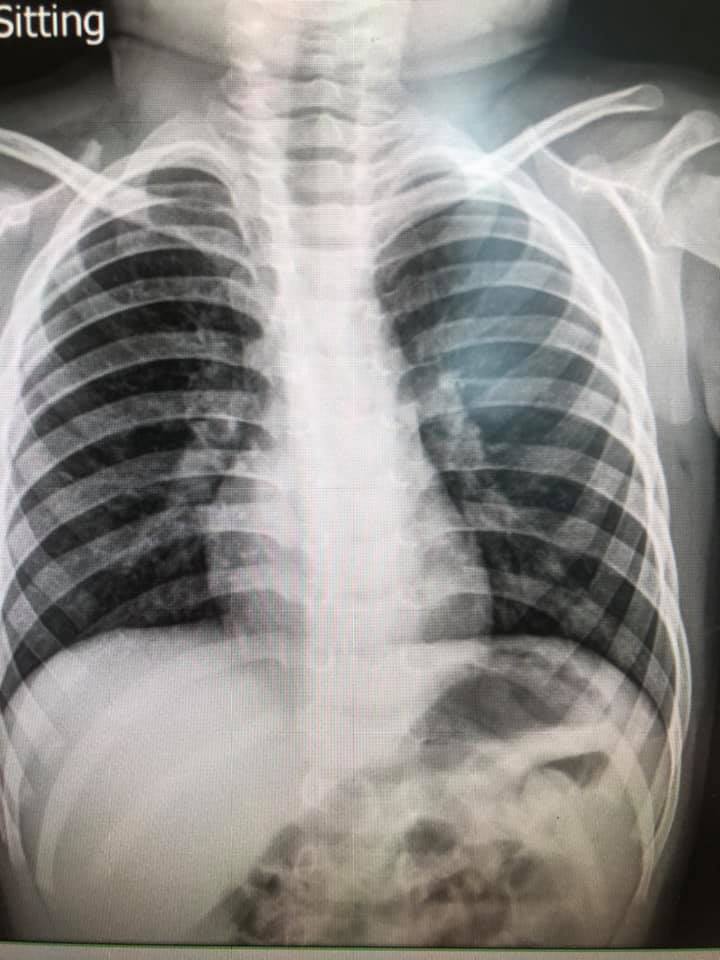

ล่าสุด วันที่ 6 พฤศจิกายน 2563 เฟซบุ๊ก Infectious ง่ายนิดเดียว ได้โพสต์ภาพฟิล์มเอกซเรย์ปอดเด็กที่ติดเชื้อไวรัส RSV 10 คน ที่เข้ารับการรักษาที่โรงพยาบาล โดยได้รับการวินิจฉัยว่ามีอาการหลอดลมอักเสบ ปอดอักเสบ โดยฝ้าสีขาวคือตำแหน่งทีติดเชื้อ สีดำคือปอดปกติ พร้อมระบุข้อเท็จจริงของ RSV ดังนี้